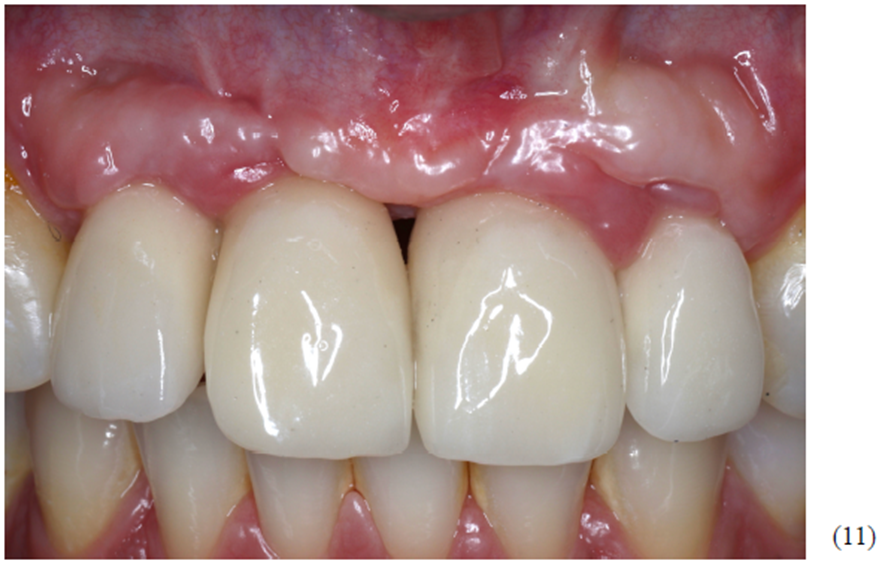

A reabilitação final ocorreu após um ano do início do tratamento cirúrgico da enxertia óssea. Foram confeccionados provisórios para preparo do perfil gengival, visando uma ótima estética do conjunto prótese/implante. Utilizamos quatro munhões do tipo Ideale, da Implacil De Bortoli, de altura 3.3 x 2.5 x 4 mm para confecção das próteses do tipo parafusada (Figura 11). A foto final foi no acompanhamento de seis meses, onde pudemos observar ótima estabilidade do tecido peri-implantar.